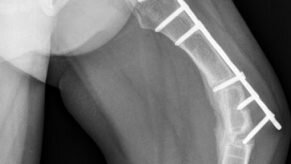

Несовершенный остеогенез – тяжелое наследственное заболевание, основным проявлением которого является нарушение структуры и прочности костей, приводящее к частым переломам костей. Дети, страдающие этим заболеванием ограничены в своих возможностях в связи с риском возникновения перелома без адекватной травмы, а также из –за деформаций конечностей. Без адекватного лечения заболевание нередко приковывает пациентов к постели, изолирует от общества, препятствует нормальному психомоторному развитию, интеграции в детских коллективах и, в дальнем, в социуме...

Несовершенный остеогенез - это редкое наследственное (генетическое) заболевание, также известное как болезнь хрупкости костей. У ребенка, рожденного с несовершенным остеогенезом, кости легко ломаются и не формируются нормально...